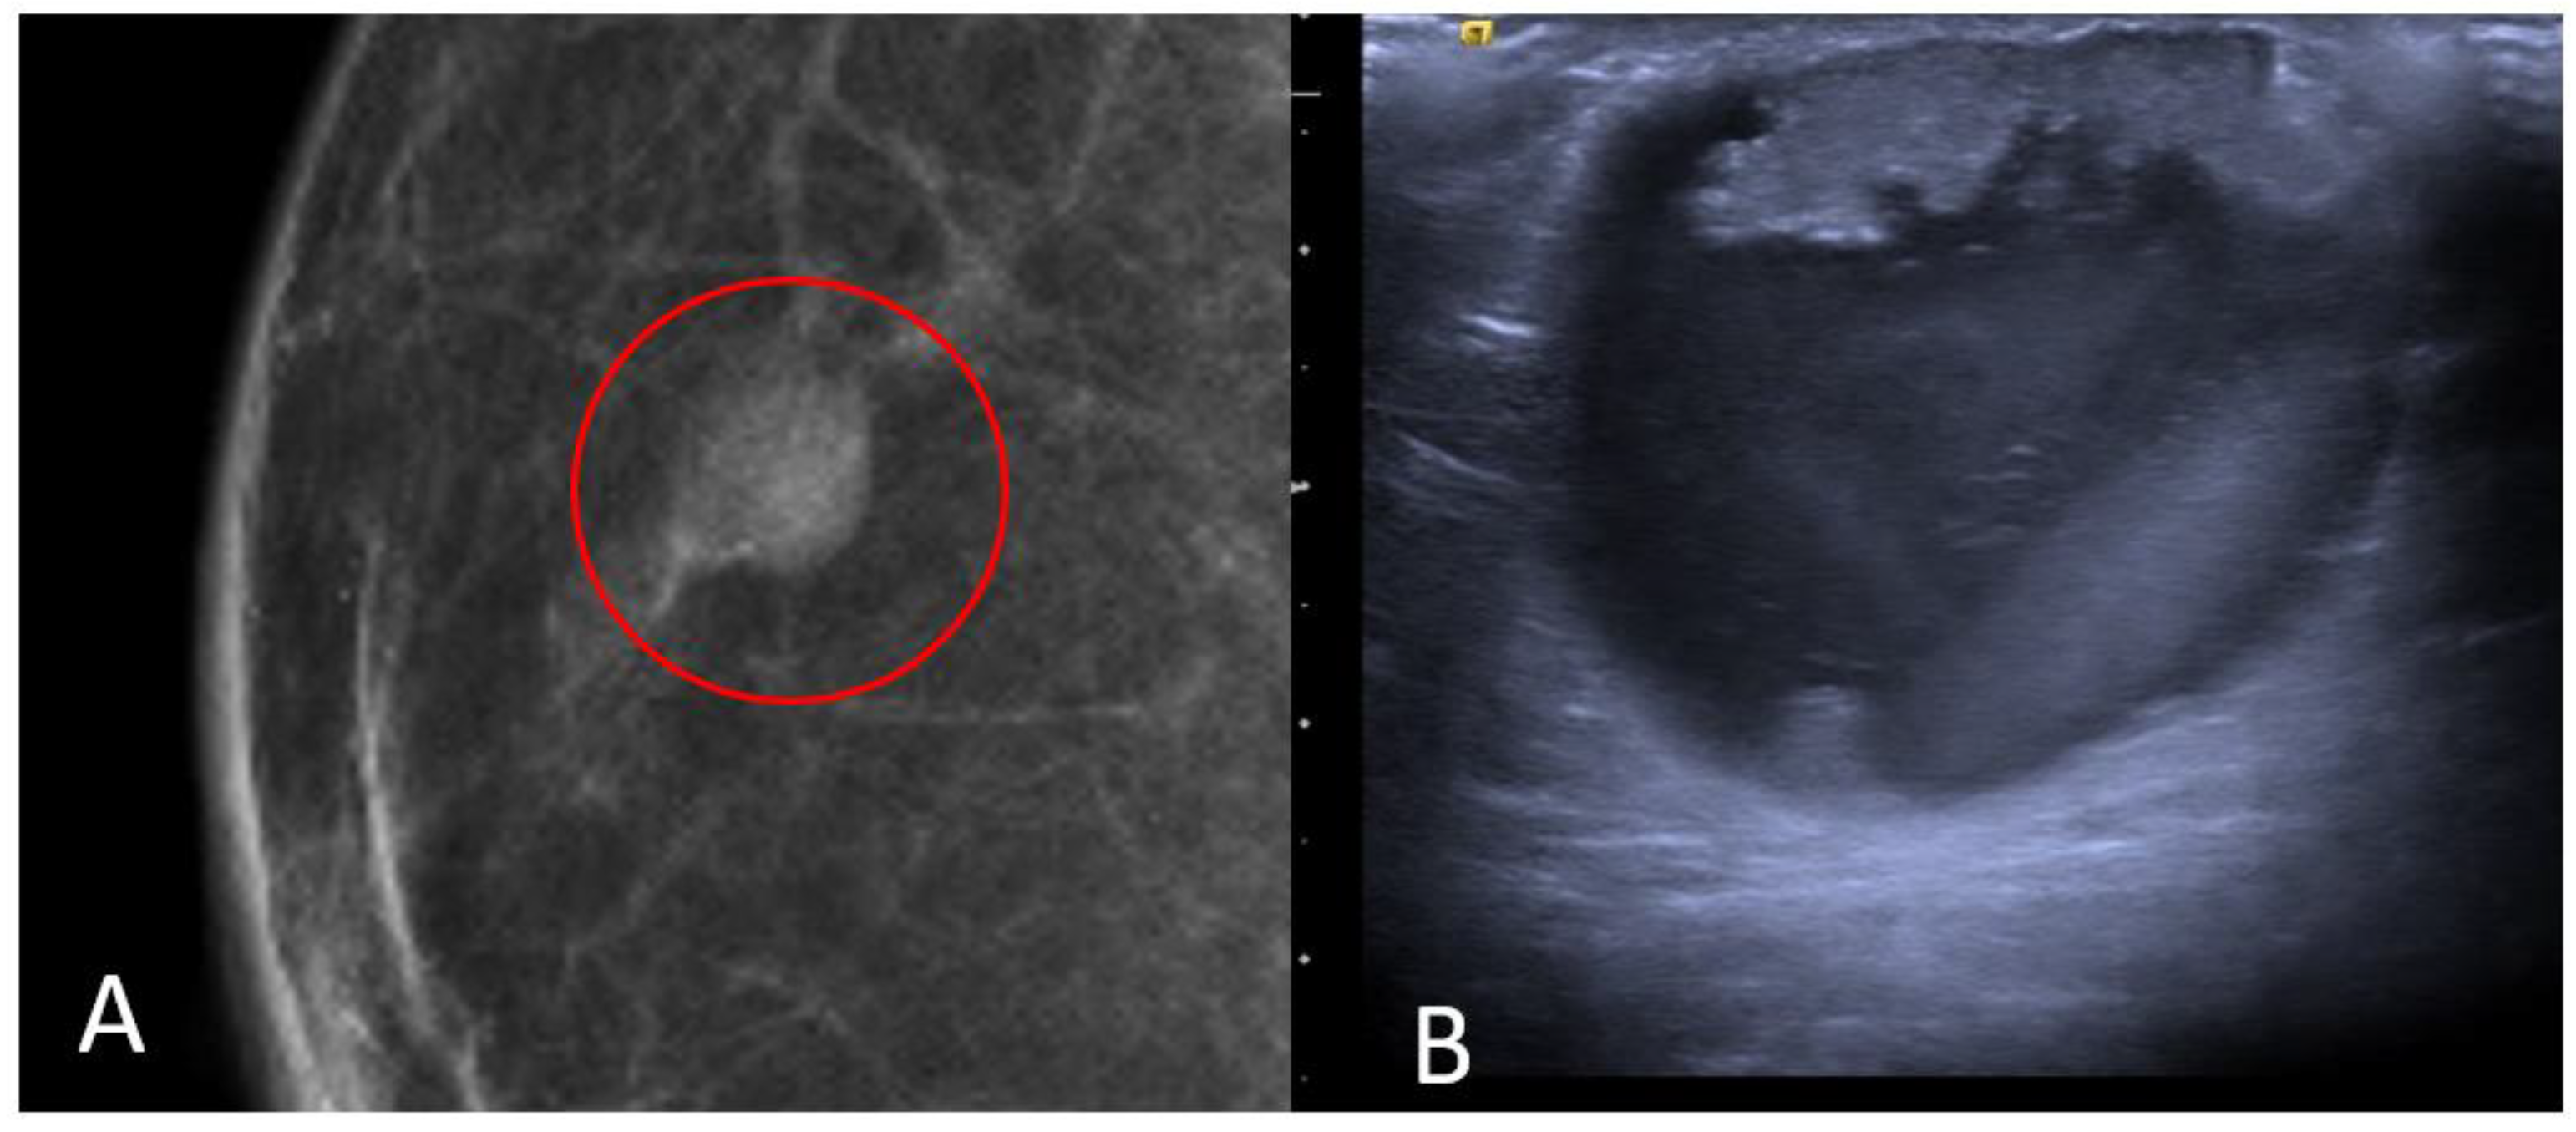

The most common histological subtype of primary malignant breast lesions in men is invasive ductal carcinoma (IDC) [27,28], shown in Figure 7.

Figure 7.

A 60-year-old man with gynecomastia presenting a retroareolar lump on the right breast with nipple retraction and without nipple discharge. Histological examination revealed an invasive ductal carcinoma (ER + 90%, PR + 60%, HER2 score 1+). Ultrasound examination (A) shows a hypoechoic irregular mass (white arrow) in the retroareolar region, with lobulated margins. A mammography (B) shows an irregular hyperdense retroareolar mass with lobulated margins (red circle).

IDC typically originates from the terminal duct–lobular unit [28,29]. Clinical features include a palpable unilateral retroareolar mass with nipple retraction and skin thickening [28,29]. Around 25% of cases may present with bloody nipple discharge [28]. IDC can be associated with ductal in situ components in up to 50% of cases [30]. Mammographically, IDC appears as a retroareolar irregular high-density mass with spiculated or micro-lobulated margins [30,31]. Unlike in women, IDC in men is rarely associated with microcalcifications due to the involution of the ductal system caused by the absence of estrogen and progesterone stimulation [28,29]. Ultrasonography reveals solid, hypoechoic, and irregular masses with margins ranging from microlobulated to spiculated [32]. Papillary carcinoma (PC) is the second most common invasive subtype of MBC and has a higher incidence in men compared to women [33]. PC is characterized by neoplastic proliferation of cells with fibrovascular stalks lacking an intact myoepithelial cell layer [34]. It typically presents with bloody nipple discharge and occurs in the subareolar region. Mammographically, PC may exhibit well-circumscribed or spiculated margins, while ultrasound imaging may reveal a dilated duct or cyst, often appearing as a complex cyst with solid papillary projections along the cyst wall [35,36] (Figure 8).

Figure 8.

Invasive papillary carcinoma in a 59-year-old man with bloody nipple discharge. Magnification of mediolateral oblique view of the right breast (A) shows a focal high-density mass with well-circumscribed margins (red circle). Ultrasound (B) shows a complex cyst with mixed solid and cystic morphologic features.